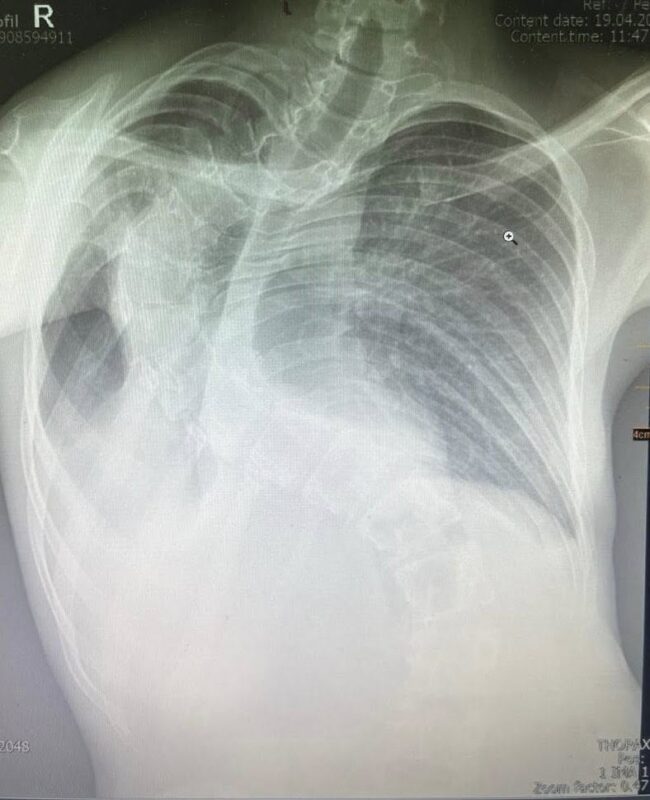

До Центру дитячої медицини у Львові, лікарні «Охматдит», звернулася 13-річна дівчинка зі скаргами на важке дихання, слабкість і незадовільне самопочуття. Попередній діагноз – пневмонія. Однак під час лікування фахівці виявили значно серйознішу причину стану дитини. На УЗД легенів лікарі помітили велике пневмонічне вогнище.

Переломним етапом стало рішення провести комп’ютерну томографію (КТ), яка і виявила справжню причину проблем: у дівчинки — глибока деформація грудної клітки зі сколіозом. Через значне викривлення хребта одна з легенів була здавлена настільки, що почалися незворотні зміни у легеневій тканині — хронічний фіброз.

До слова, глибока деформація грудної клітки зі сколіозом — це складне викривлення хребта, при якому порушується не лише його осьова лінія, а й форма та симетрія ребер і грудної клітки. У таких випадках ребра можуть з одного боку виступати, а з іншого — западати, що спричиняє зміщення внутрішніх органів, ускладнення дихання та порушення серцево-судинної діяльності.